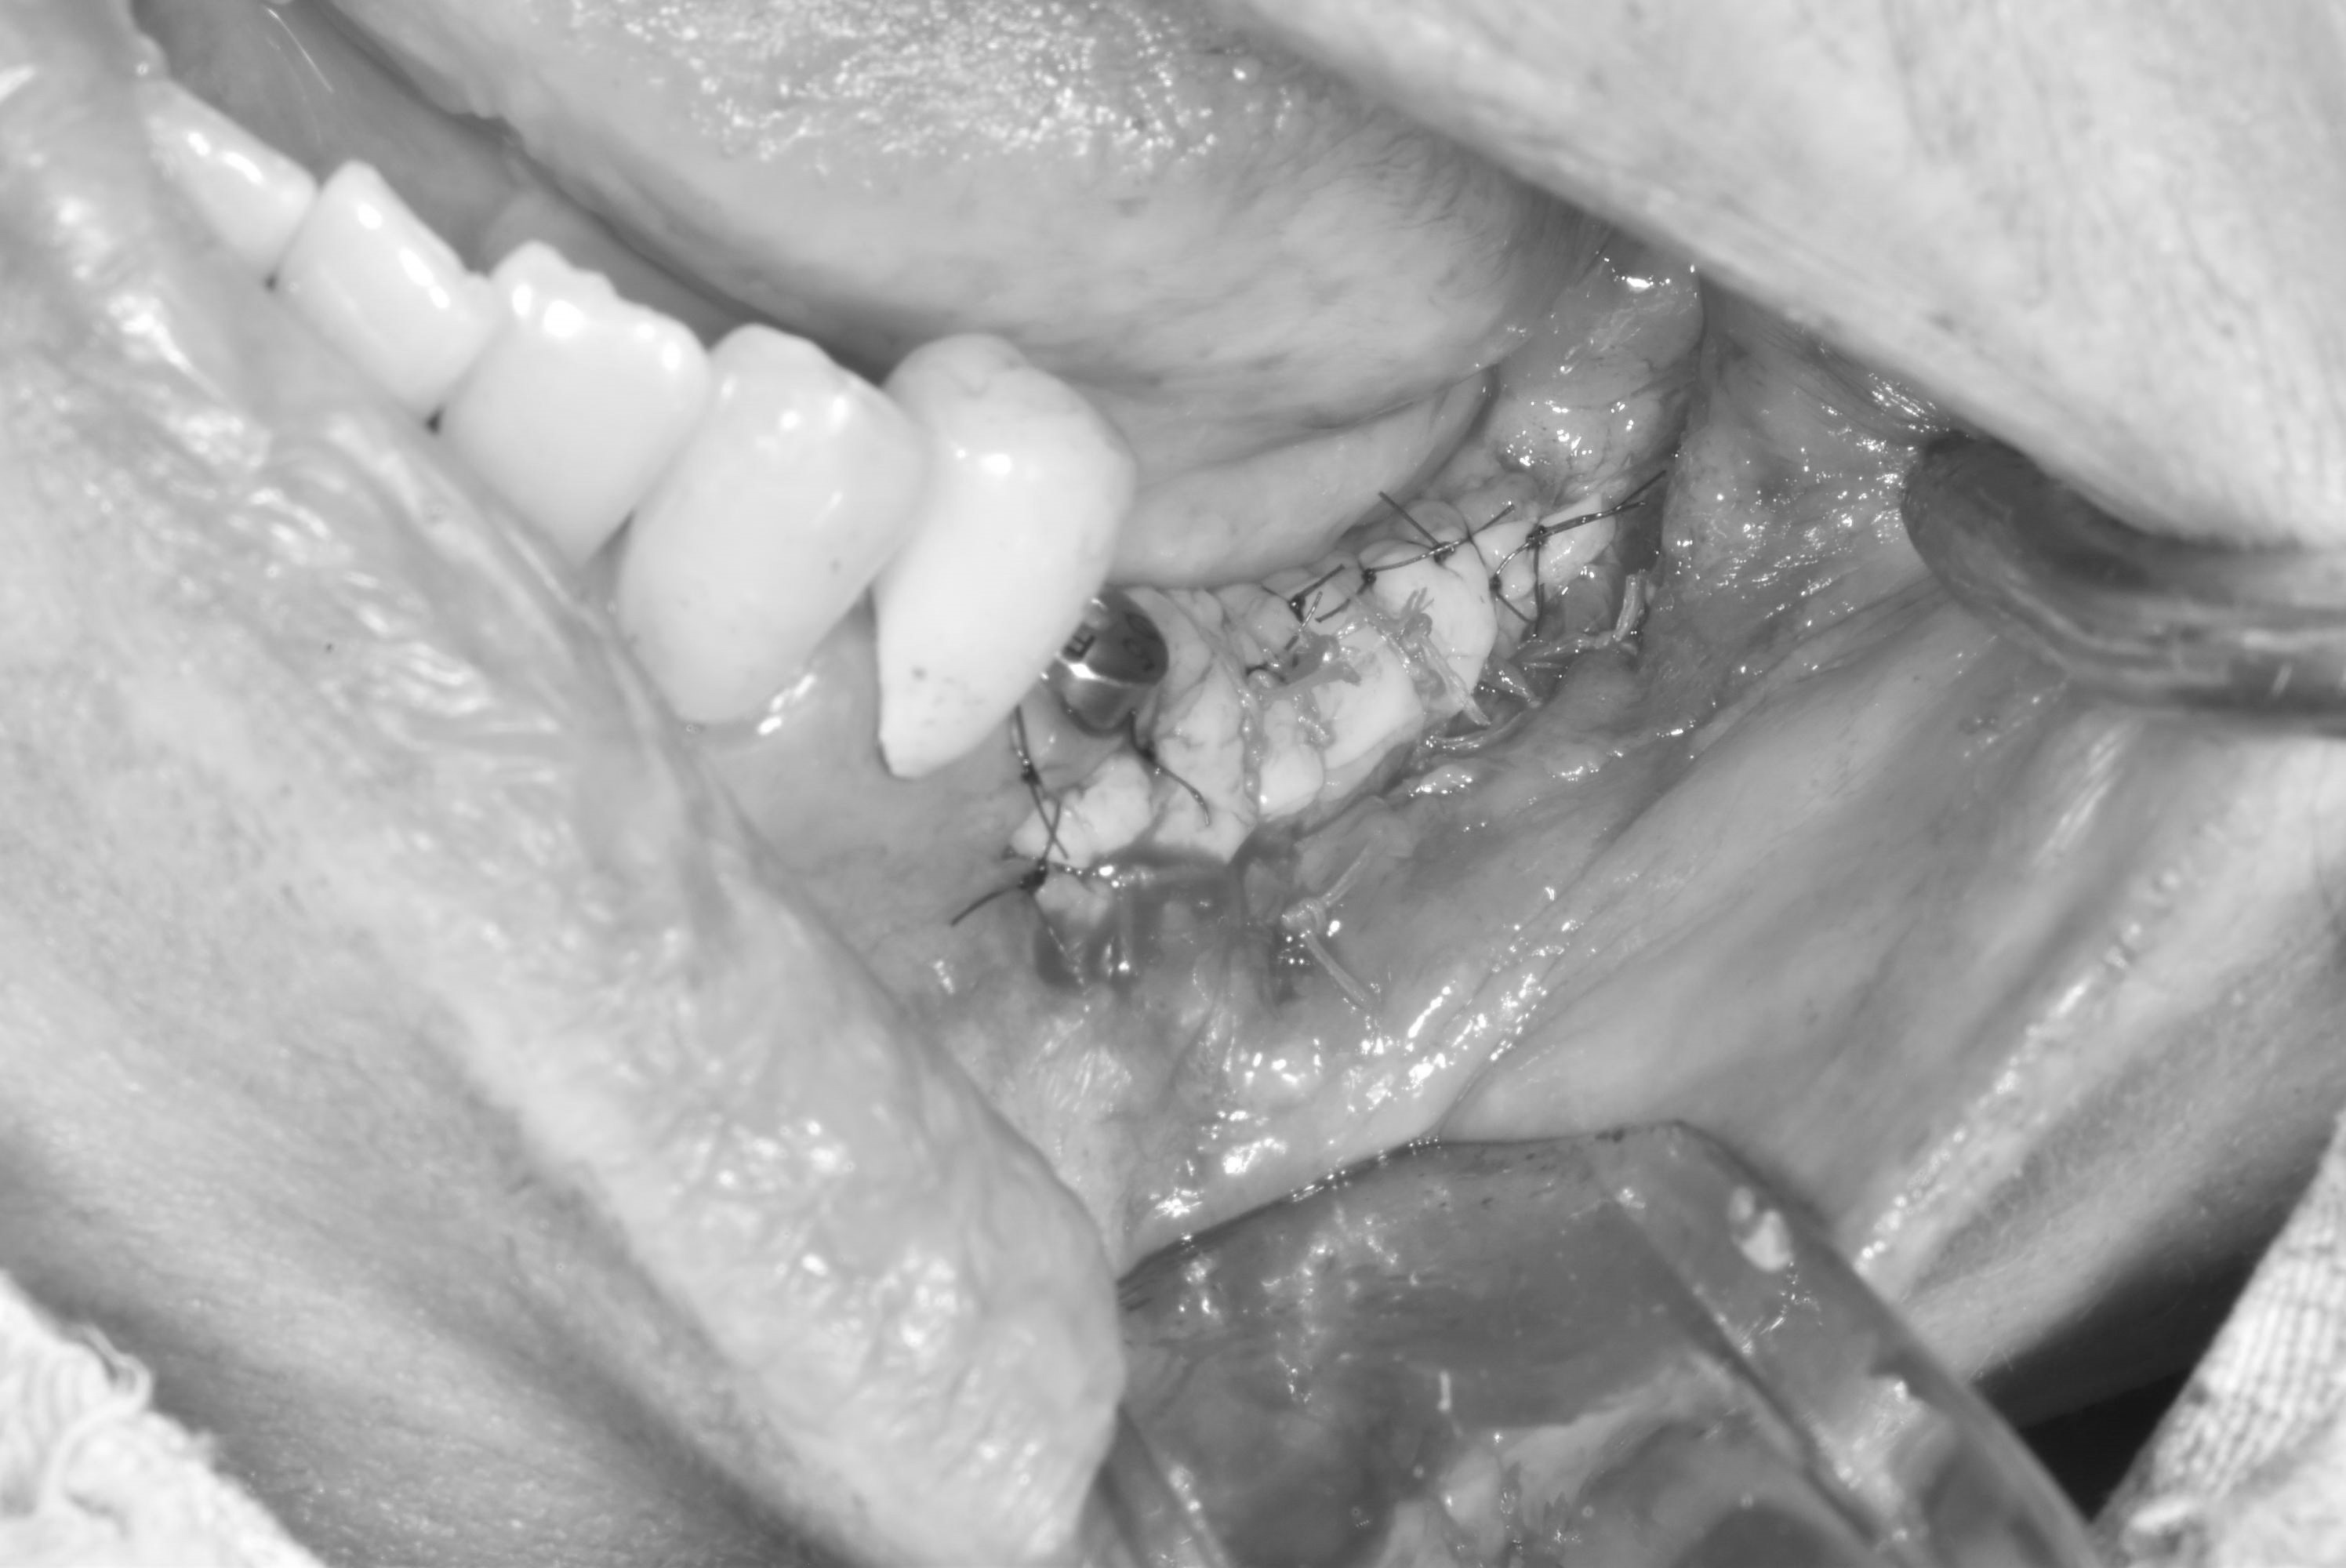

牙齦移植術(補肉)

手術案例

術前加術後案例

案例三